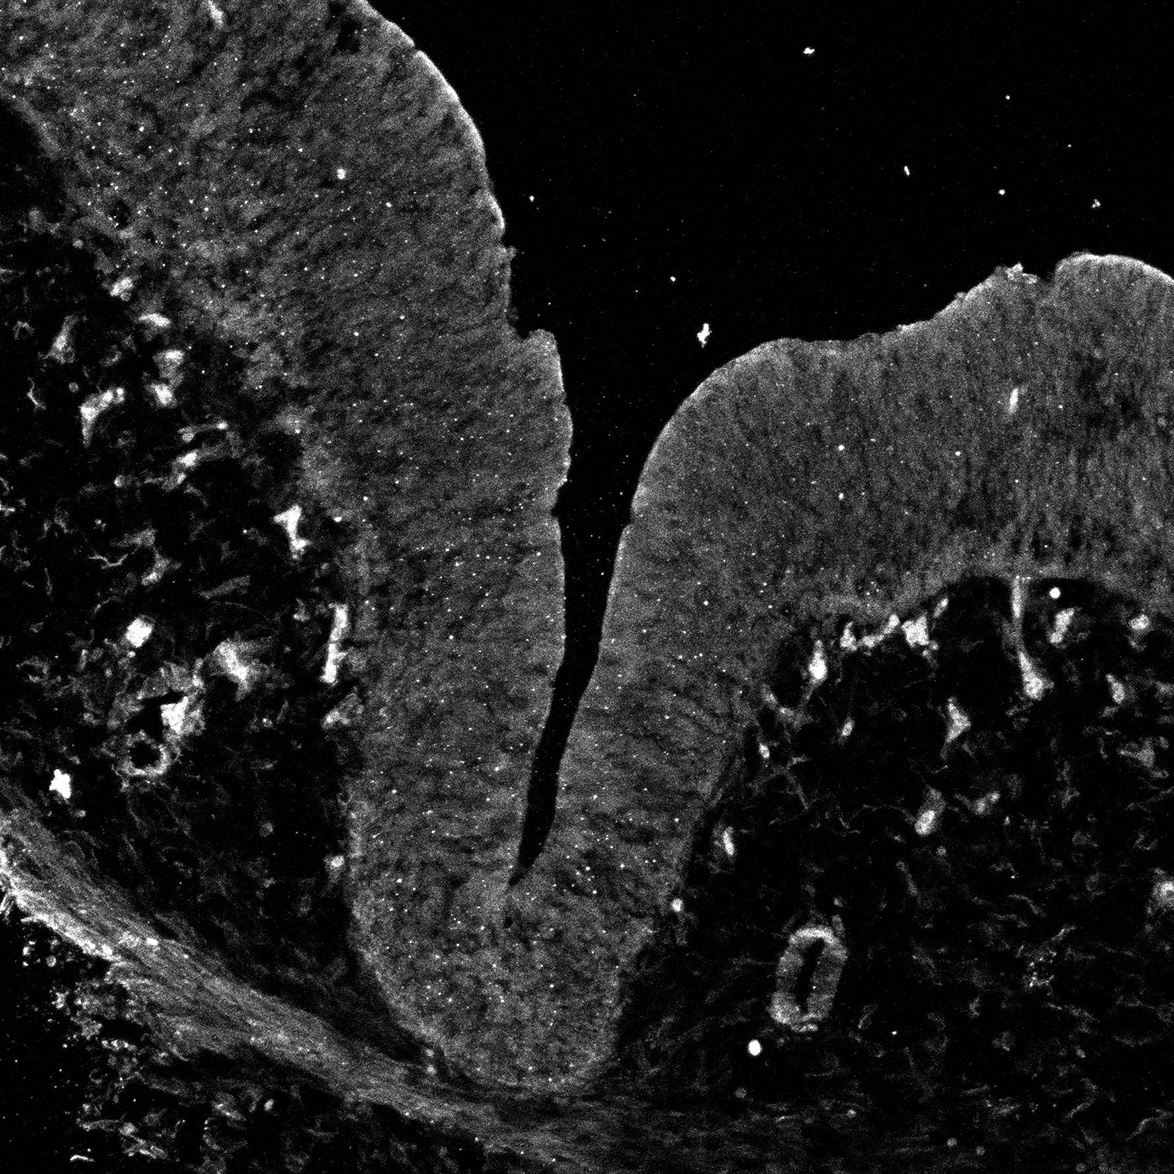

DAPI

11PCW human midbrain

MAP2

SOX2

Merged

TH